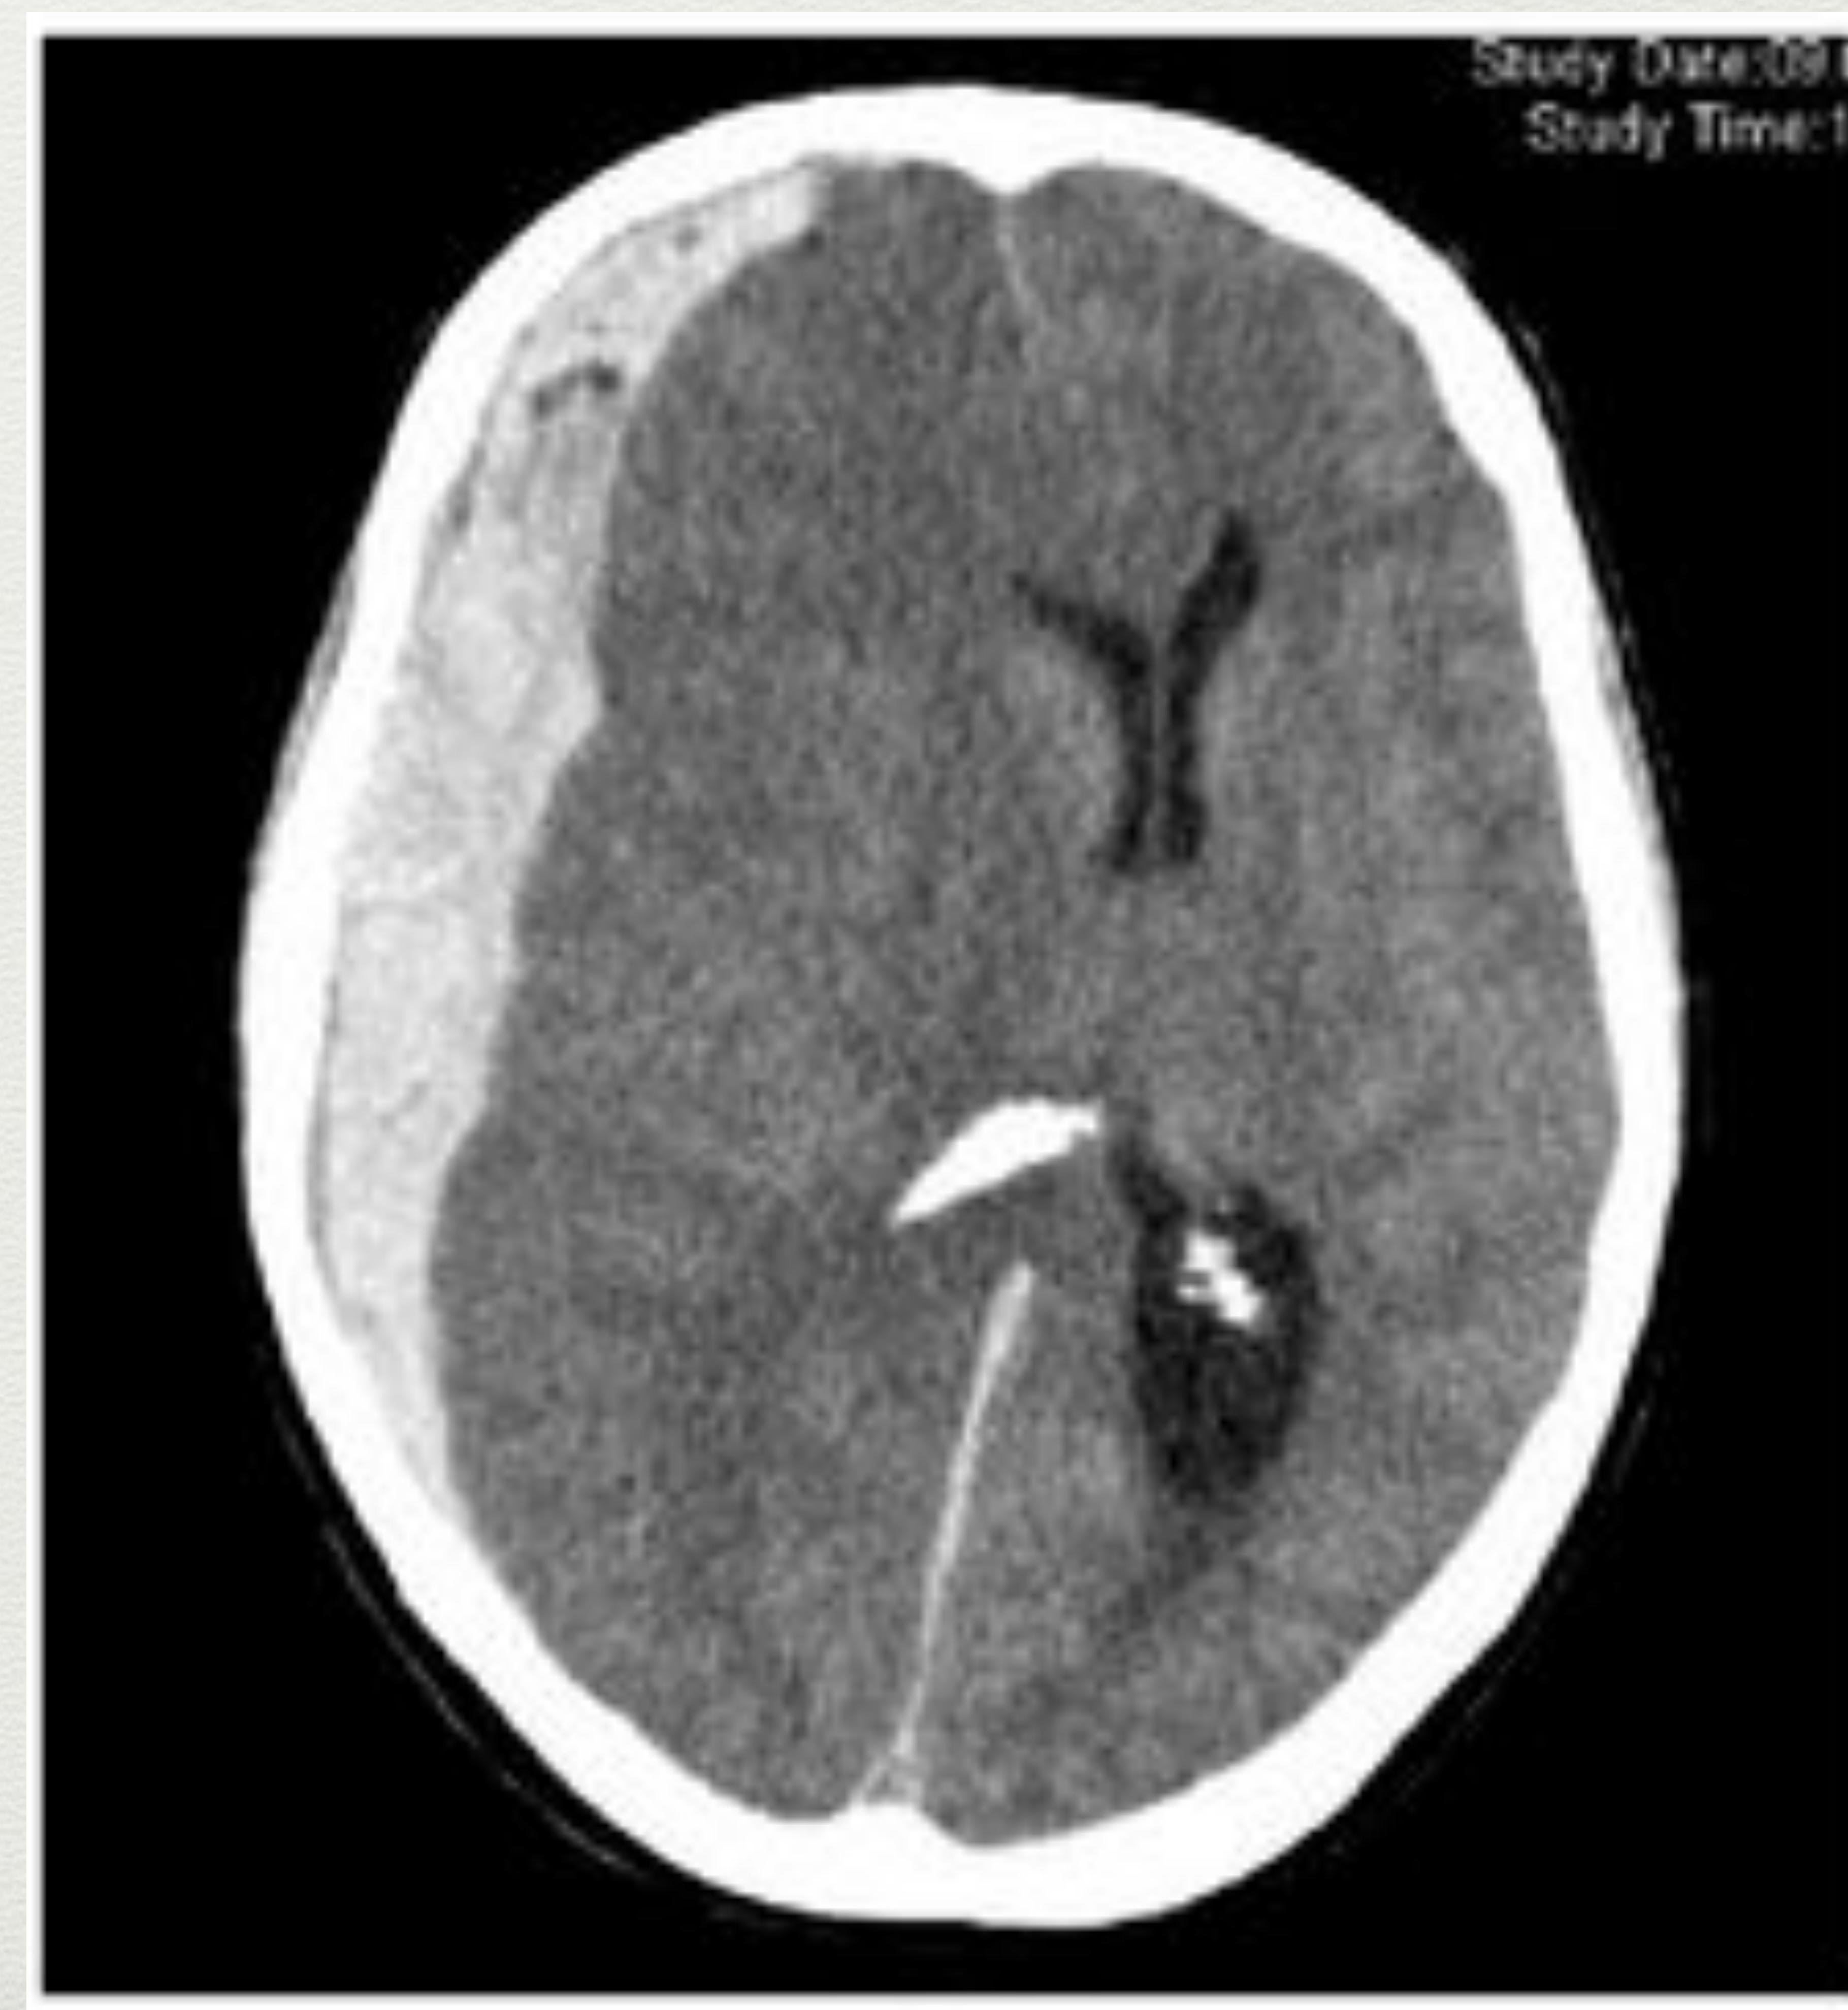

Subdural Haematoma (SDH)

- Tearing of bridging veins.

- Common in age y/o (mild trauma causes injury because brain shrinkage makes veins fragile).

- Doesn’t expand to contralateral hemisphere.

- Often associated with cerebral contusion underneath.

- Appearance: Crescent shape (Moon Shape) + shifting of midline.

Axial CT scan showing a subdural hematoma as a crescent-shaped hyperdense collection.